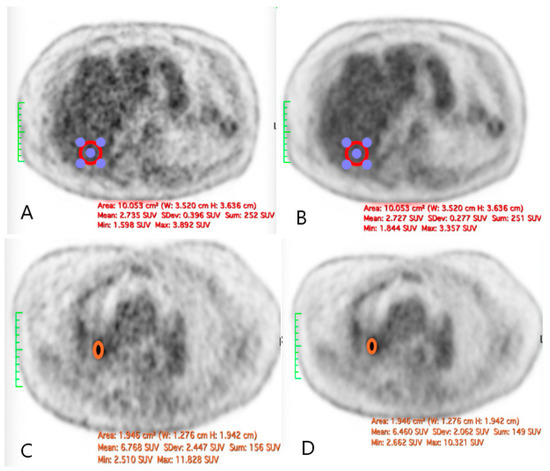

For 18F-FDG

The quantitative assessment of the image quality demonstrated a significant enhancement following SubtlePET™ processing. The SNR improved from 11.2 in standard non-denoised images to 18.5 post-denoising. Similarly, the CNR increased from 5.1 to 8.9, reflecting an enhanced lesion conspicuity against the background activity. These objective metrics align with the improved Likert-scale image quality ratings and support the clinical utility of AI-based denoising in routine 18F-FDG PET imaging. An illustrative figure of a case of a right hilar lesion and a figure comparing the SNR before and after SubtlePET™ are provided (Figure 5 and Figure 6)

Figure 5. The illustration of a case of difference in the SNR before and after the application of SubtlePET™: ((A): liver VOI without AI denoising; (B): liver VOI with AI denoising; (C): right hilar lesion without AI denoising; (D): right hilar lesion with AI denoising).